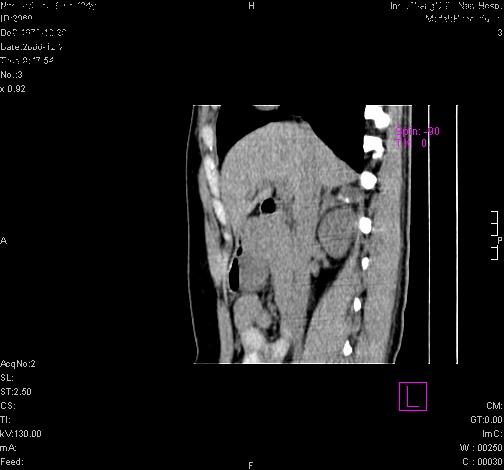

标题: CL0340:【】肾上腺囊肿,比较典型。

患者为年轻女性,查体发现右侧肾上腺囊性占位。无临床体征。

这么漂亮的图像,一看一目了然。典型的右侧肾上腺囊肿,周围有钙化。感谢搂主!

这么明显的弧形钙化,多考虑包虫病所致的寄生虫性囊肿。

右侧肾上腺囊性密度灶囊壁有钙化。考虑肾上腺囊肿,结核?

右侧肾上腺囊肿,周围有钙化。